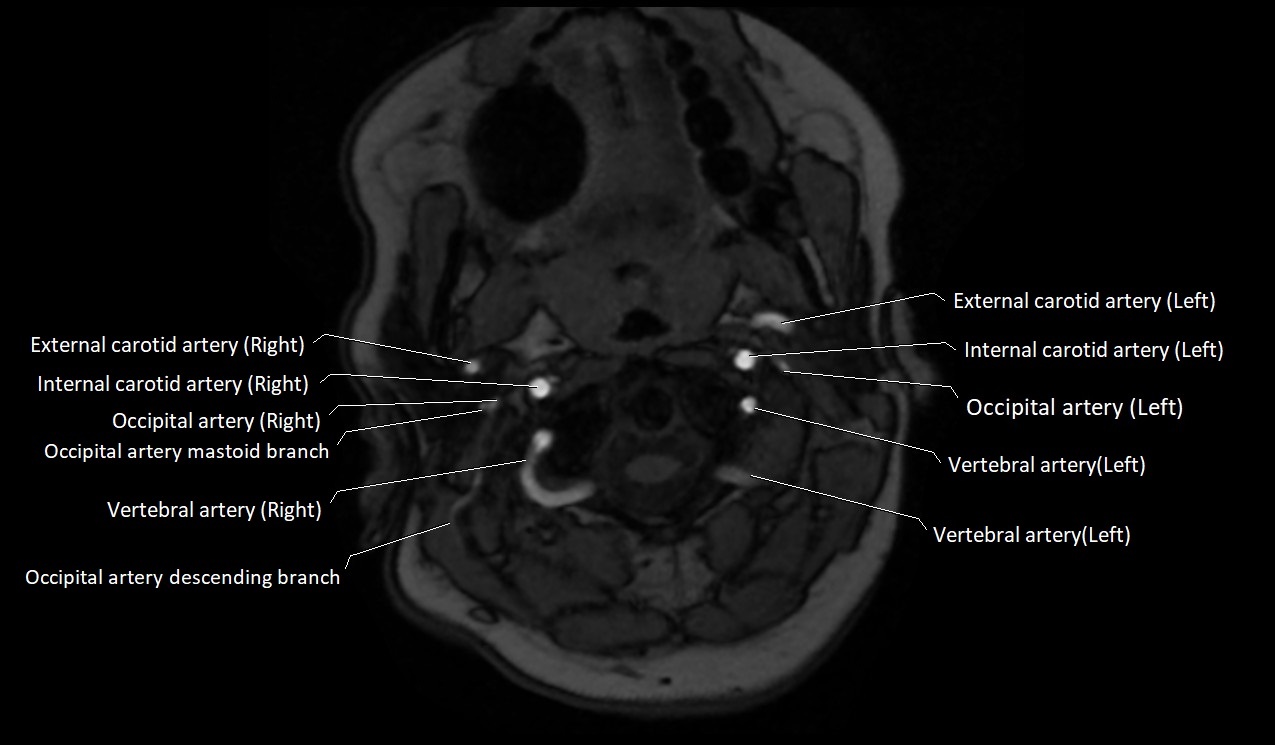

MRI images

image